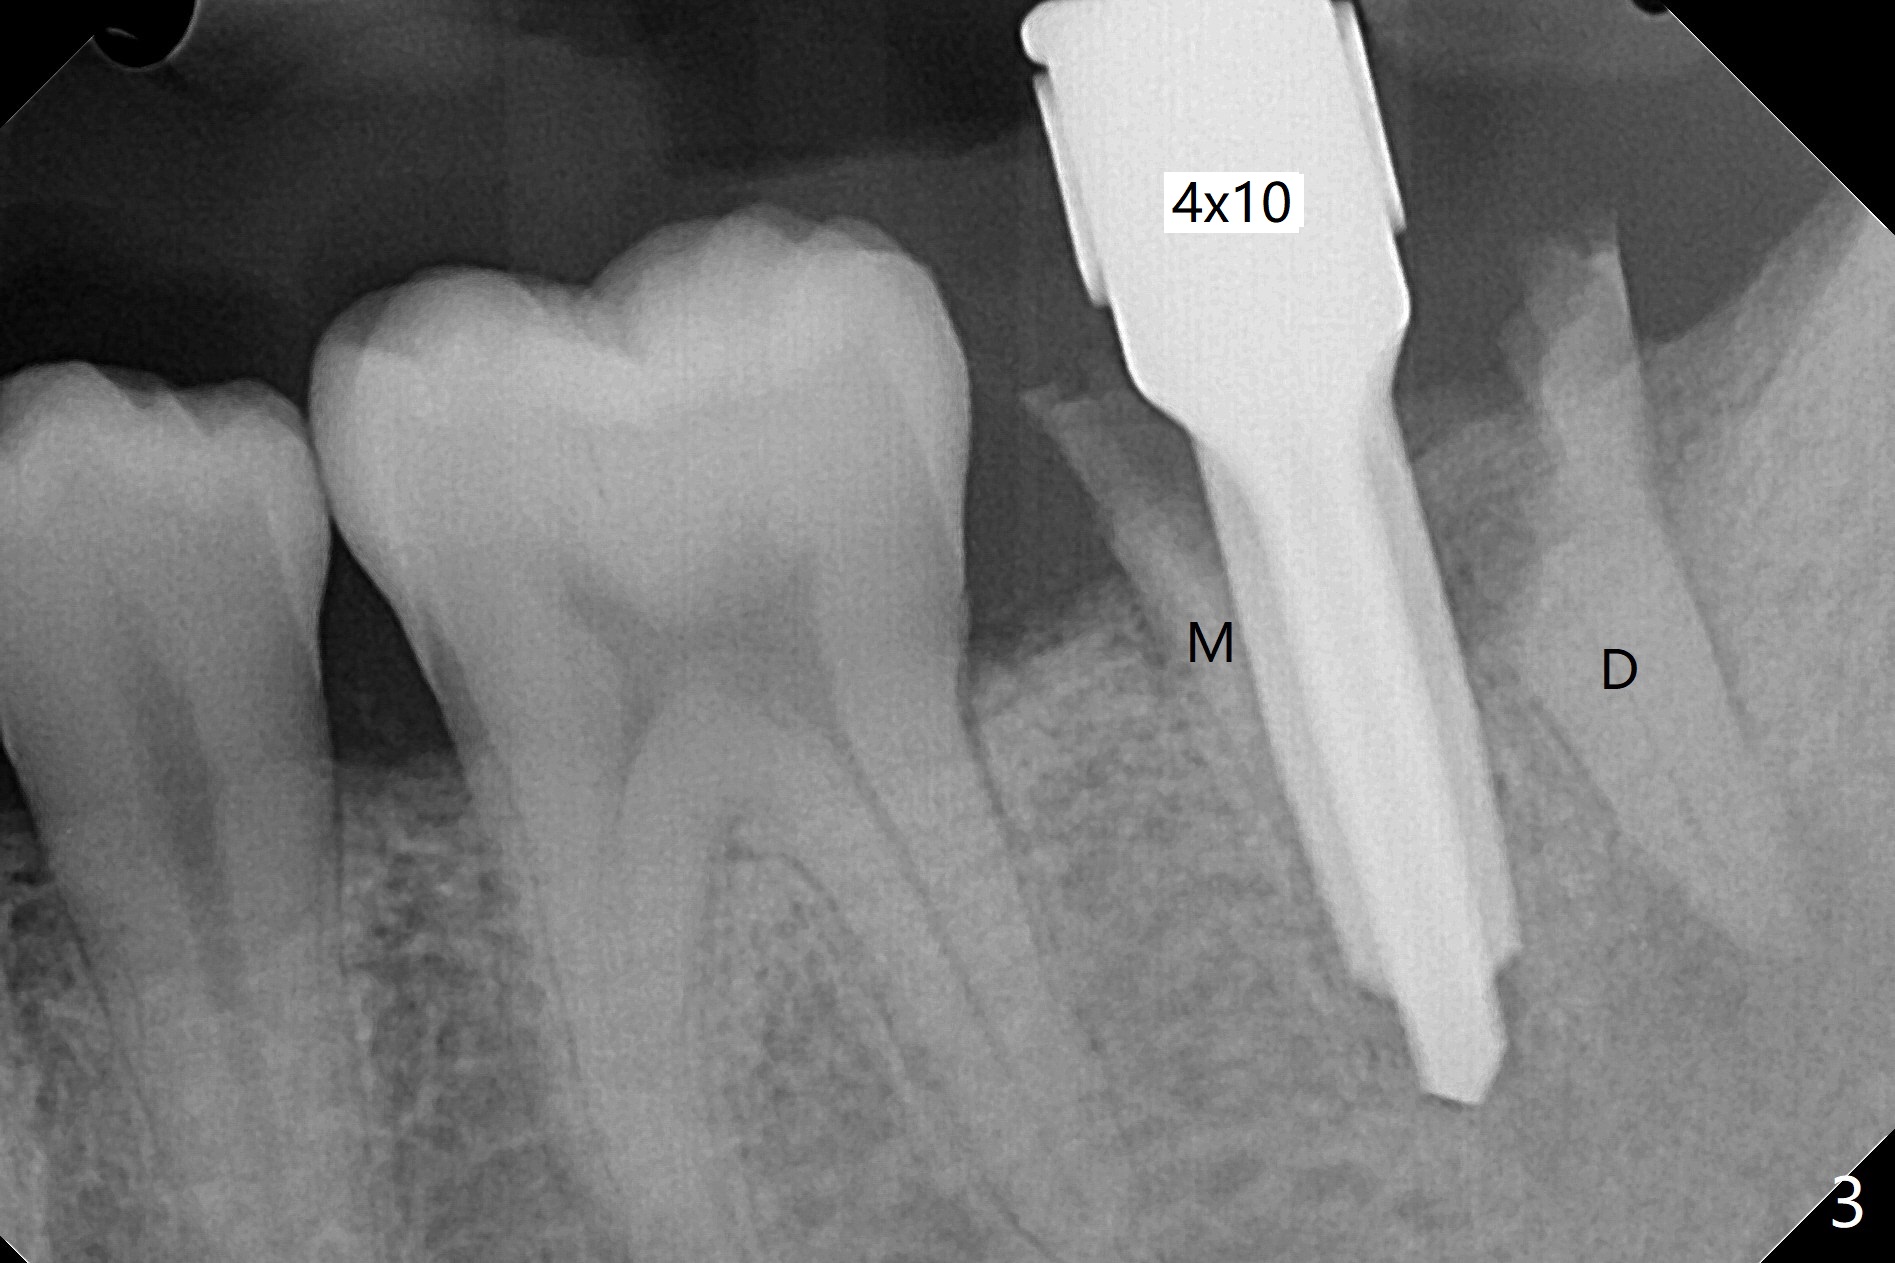

即刻种植即刻修复偶尔出现骨粉丧失,今天我们尝试临时基台,它可以制作像螺丝固位牙冠,可能会减少骨粉流失。左下7颊侧肿胀(图一:*),为了让植体(图二:绿色)植入中隔正中,钻洞时保留近中(M),远中(D)牙根。但是意想不到的是在导板指引下,钻头还是偏移近中(图三),而且颊侧(图四:圆圈),不过颊侧骨板没有缺损。由于牙根存在(硬),钻洞吃力,之后拔除,完成最后一个钻头,放置植体(图五),方位仿佛不错,临时基台(5.2x8(2)毫米)也完全就位,树脂围绕基台制作临时牙冠(图六),最后使用螺丝固位(*),颊侧肿胀牙龈必须用缝线固定(<),减少骨粉损失。由于牙冠与基台连接不好,病人汇报有些骨粉丢失。术后一个月检查尚可愈合正常,病人满意,已经做好思想准备做右下第二磨牙种植。临时牙冠进行修整。术后即刻近中牙槽窝间隙由粘性骨粉充填(图五),四个月后间隙消失(硬骨板也消失,图七),5.2x5(3)毫米粘固基台似乎没有完全就位,可能因为远中牙槽嵴阻挡(图七:*)。小一号基台仿佛完全就位(图八(咬翼片);图七(根尖片,可能失真)),但是临床上没有听到清脆声音(可能软硬组织阻挡)。随着时间推移,远中牙槽嵴吸收,当松动基台螺丝再次拧紧,可能会真正完全就位,必须拍摄完美咬翼片证实。这种植体芯(body, not threads)特别厚内部结构看不清楚。两周后粘固牙冠,然后取出牙冠和基台,清除残余粘固剂,然后复位,拧紧30Ncm。